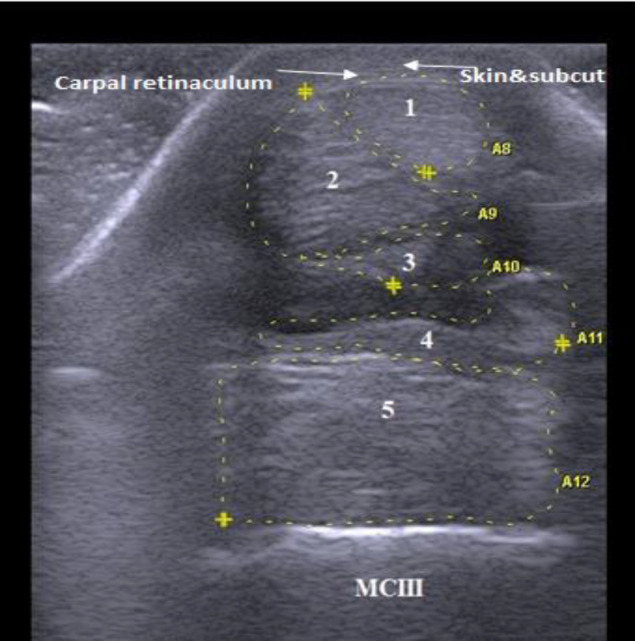

Methods: B-mode ultrasonography was conducted for the proposed tendons and ligaments in 12 clinically normal donkeys. Targeted structures were examined using transverse and longitudinal scans and evaluated in shape, echogenicity, echogenic pattern, fiber alignment pattern, and cross-sectional area (CSA).

Results: Using transverse scan, the sonographic shapes of tendons and ligaments of metacarpal and metatarsal regions were determined. Upon examining different levels of each region, specific ligaments, not tendons, were present only at the higher levels. The echogenicity of ligaments and tendons was either similar or variable across different levels. All tendons and ligaments displayed homogeneous echogenicity except for the suspensory ligament. In the longitudinal scan, tendons maintained linear and parallel fiber alignment along examination levels. Conversely, ligaments displayed mostly inconstant fiber patterns (linear/crimp). There was a statistically significant (P<0.05) difference in CSA of tendons and ligaments between certain levels within metacarpal and metatarsal regions. Upon comparing metacarpal and metatarsal regions, there were distinct variations in some ultrasonographic characteristics of the same tendons and ligaments.